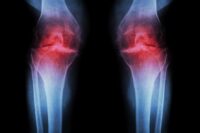

Scientists Find Ultrasound Could Prevent Arthritis Onset

Summary of Scientists Discover Ultrasound May Stop Arthritis Before It Starts: Researchers at The University of Alabama in Huntsville have found that continuous low-intensity ultrasound may help reprogram immune cells…